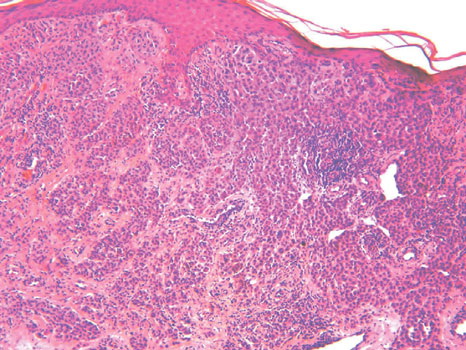

Read MoreNeutrophilic dermatosis= الجلاد بالمعتدلات Sweets Syndrome and Sweets Like Neutrophilic Dermatosis Dr. R. D. Sweet described in 1964 a disease process, which he termed “acute febrile neutrophilic dermatosis,” that was characterized by abrupt onset of fever, leukocytosis, and erythematous plaques infiltrated by neutrophils . This condition typically occurs in middle-aged women after nonspecific infections of […]